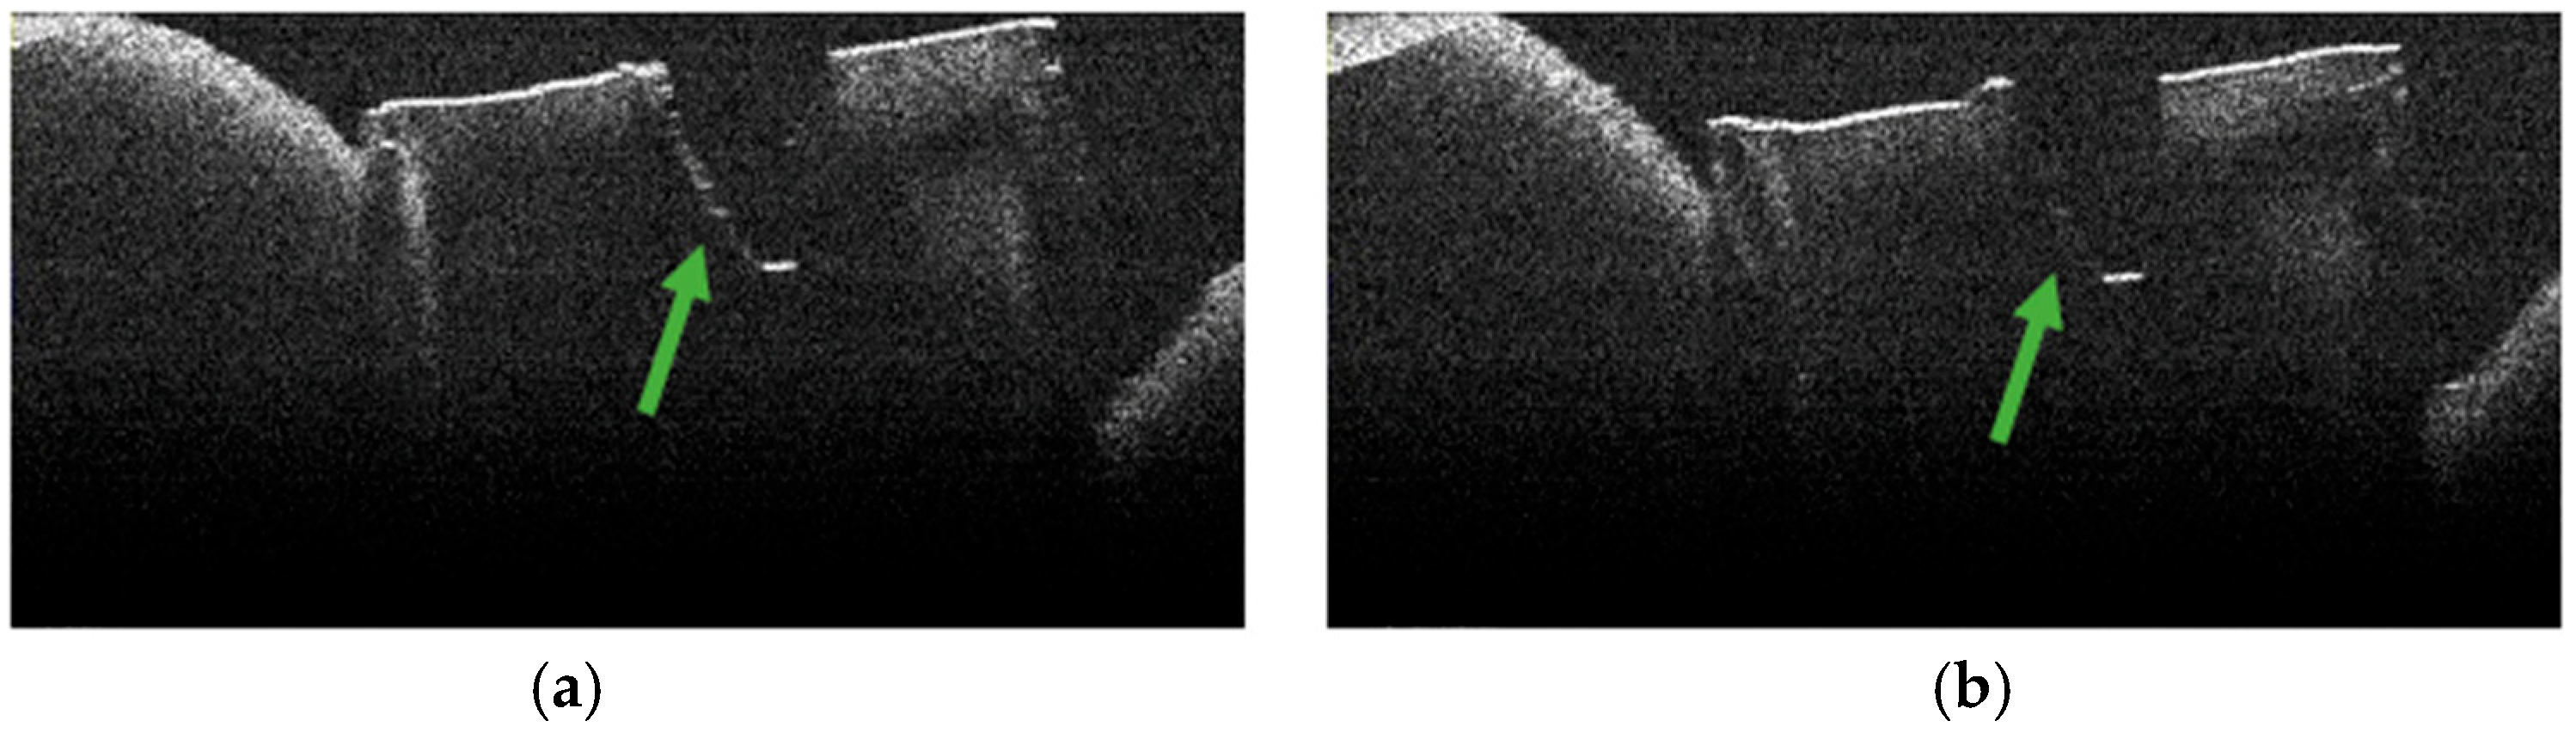

3.5. OCT Examination of Specimens from Group B

3.2. Defining OCT Signatures: Alterations vs. Artefacts